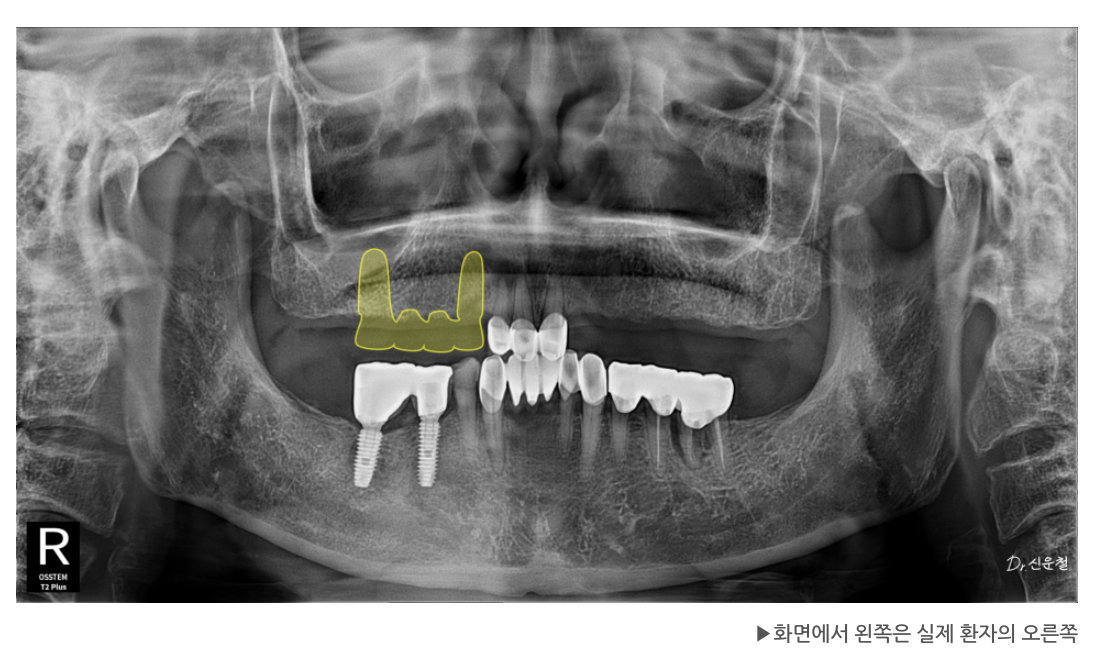

[오른쪽 치료 과정]

4개 상실 → 임플란트 3개로 복원

오른쪽은 치아가 4개 연속으로 빠져 있었습니다.

하지만 이를 한 번에 길게 연결하면

힘이 집중되어 오래 버티기 어렵습니다.

그래서

✔ 뒤쪽 힘이 안정적인 두 자리에만 임플란트를 식립

✔ 3개 치아 역할을 할 수 있도록 다리 구조로 제작

했습니다.

남은 앞쪽 1개는 단독 임플란트로 자연스럽게 회복했습니다.